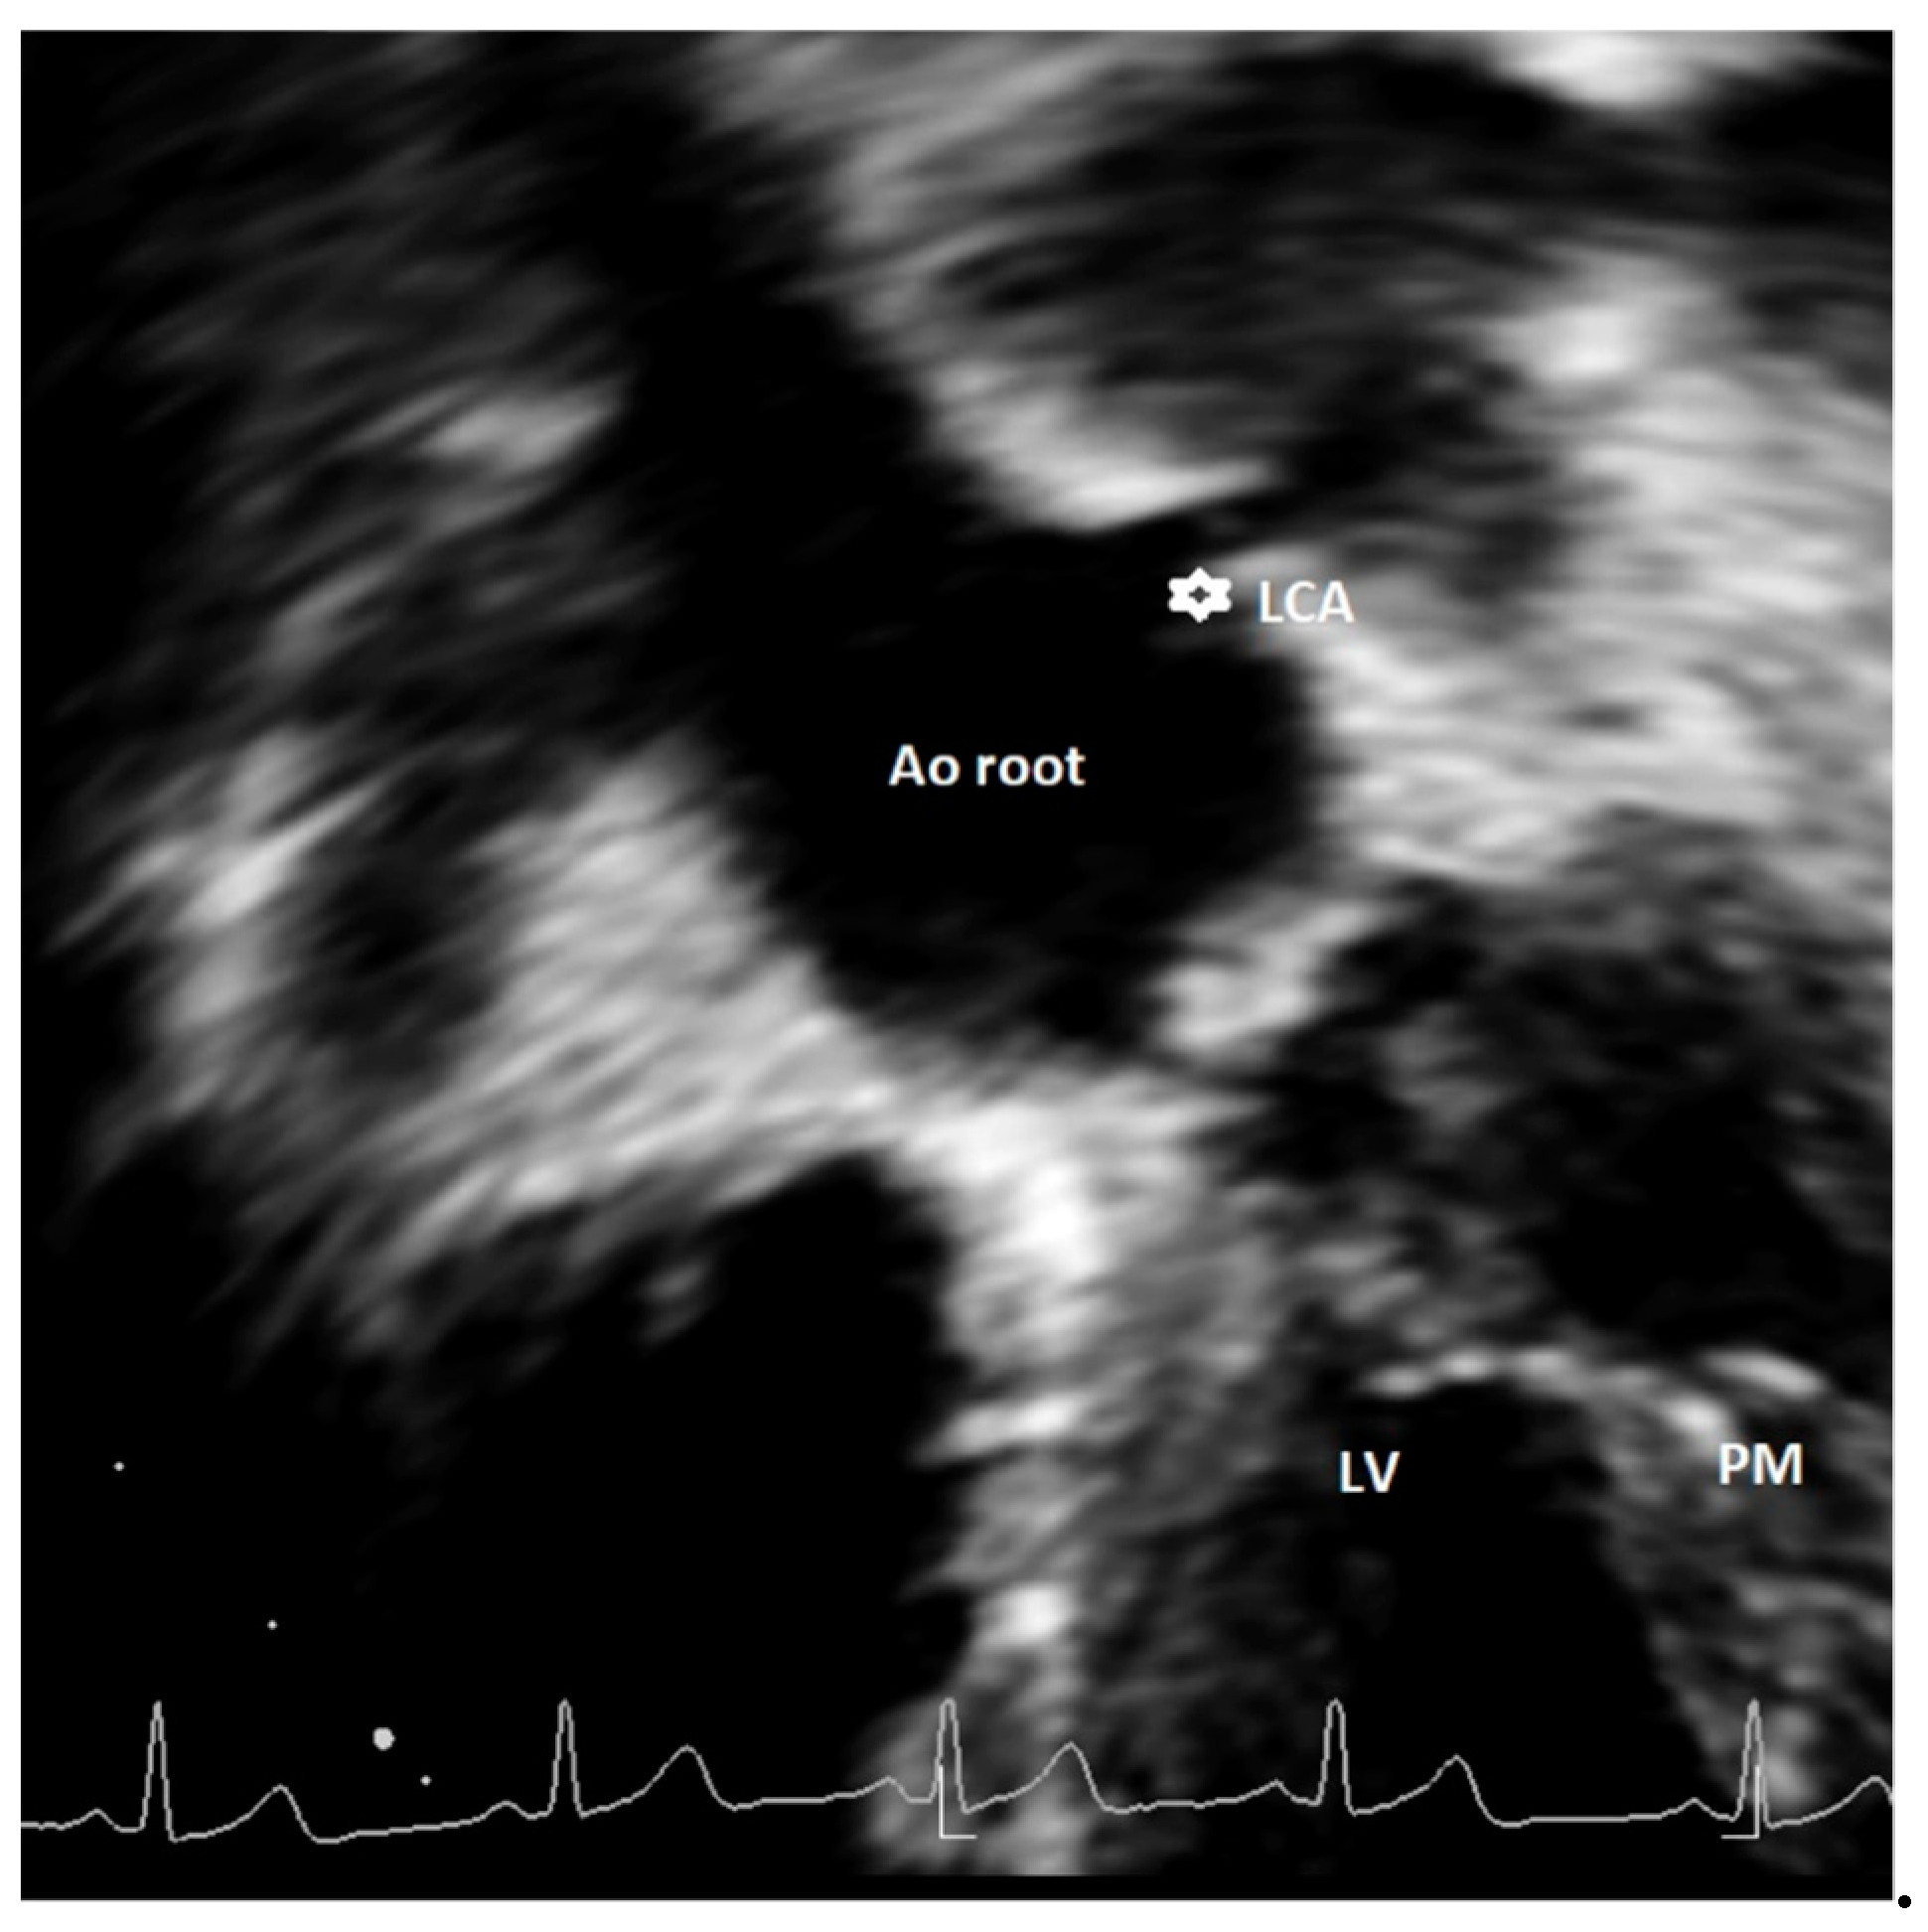

Figure 1. An asymptomatic 14-year-old boy evaluated with negative stress test for murmur at routine soccer screening. Origin of the left common artery (LCA) from the right sinus of Valsalva was incidentally discovered at echocardiography ((a,b)—short-axis view with slightly different angulation) and confirmed by Coronary Computed Tomography Angiography (CCTA) (c). RCA = right coronary artery; LCA = left common artery; RCS = right coronary sinus; AO = aortic root; RVOT = right ventricle outflow tract.

Major AAOCAs were usually defined as RCA and LCA origins from opposite wrong sinus (Figure 1), a single ostium coronary artery, or left circumflex artery (CFx) originating from right coronary sinus [14,15,20,23,24,31]. The detection rate of major AAOCAs greatly varied among the different studies, from 0.0% [15,24,31] to 0.09% [20] and up to 0.76% [23]. The positive predictive value of echocardiography (with confirmation at either coronary angiography or CT angiography) in the diagnosis of major AAOCAs was high, varying from 87.5% [21] to 100% [20].